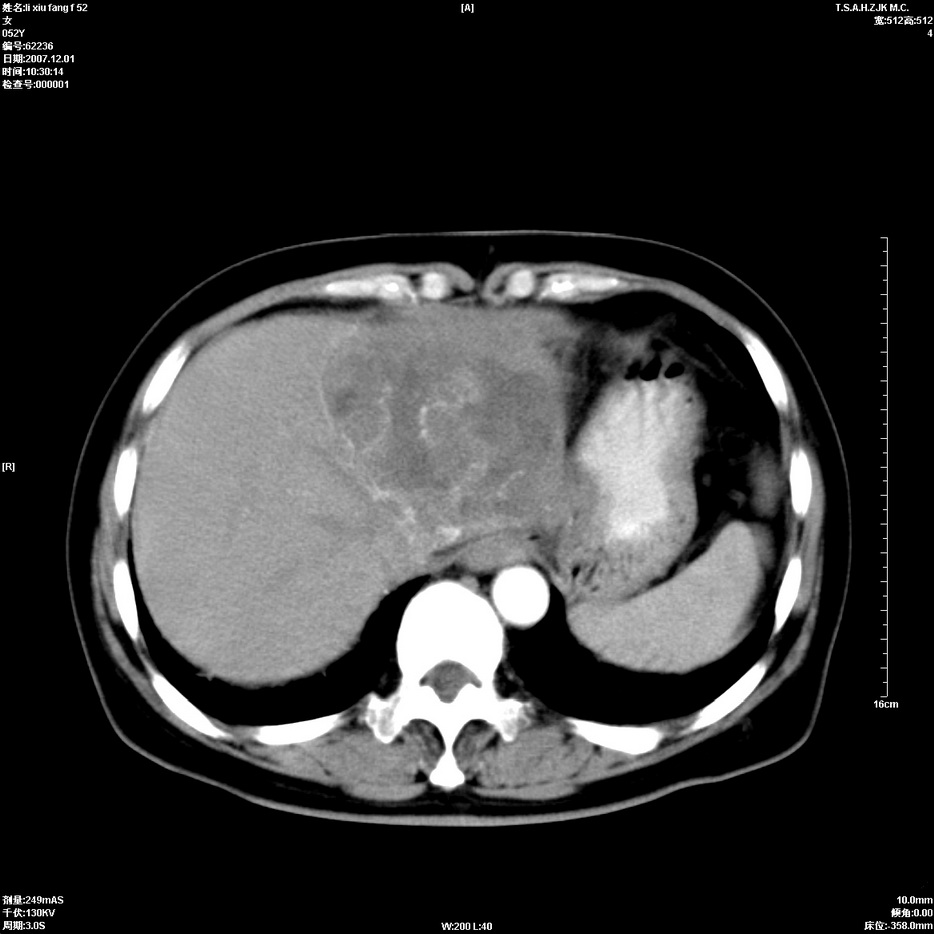

标题: CT12858:女,52岁,胎甲球蛋白861肝左叶占位,肝癌。下腔静 [打印本页]

标题: CT12858:女,52岁,胎甲球蛋白861肝左叶占位,肝癌。下腔静

肝左叶巨大低密度灶肿块,增强符合快进快出表现,有动静脉交通支;静脉期,下腔静脉内有充盈缺损,afp明显升高,支持肝癌并下腔静脉癌栓形成。

以下是引用拾荒者在2008-4-15 22:57:00的发言:[br]肝左叶巨大低密度灶肿块,增强符合快进快出表现,有动静脉交通支;静脉期,下腔静脉内有充盈缺损,afp明显升高,支持肝癌并下腔静脉癌栓形成。